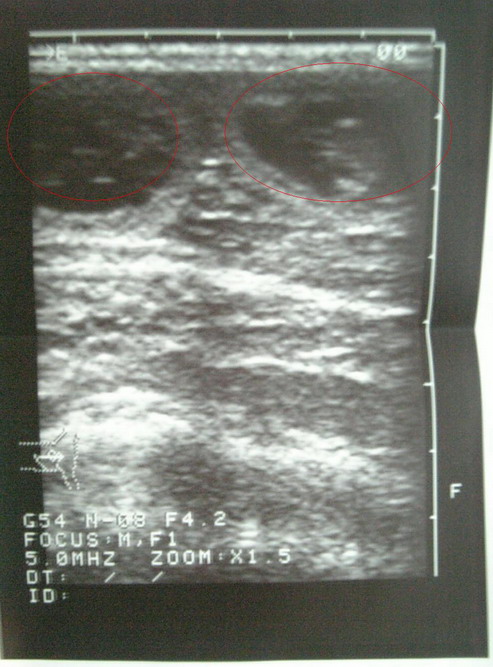

然後就剃毛!! 做了超音波檢查!! 雖然不清楚

但還是可以隱隱約約看到有4ㄍ點點!!醫師說那是胎盤

目前照出來!! 大概是四胎左右!! 可能重疊 可能更多

目前看到就是4胎!!! 開心>"<

圖片上 圈起來的地方  就是胚胎!!   這是左邊的  兩顆

右邊也有兩顆!胚胎!!!   可是令一邊依樣 所以就沒放上來了

目前看到這張是兩ㄍ 胚胎!!